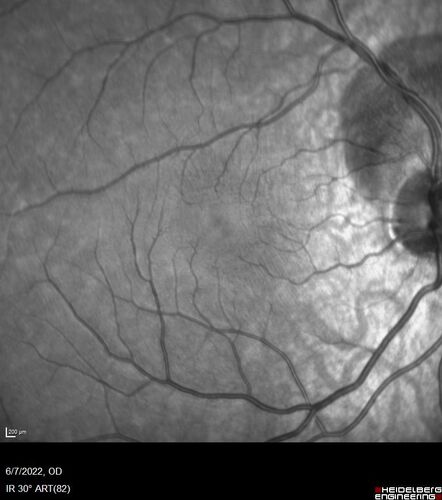

Traumatic Peripapillary Subretinal Hemorrhage

16 year old hit in eye with finger during basketball. Vision is 20/25 and there is a peripapillary hemorrhage.